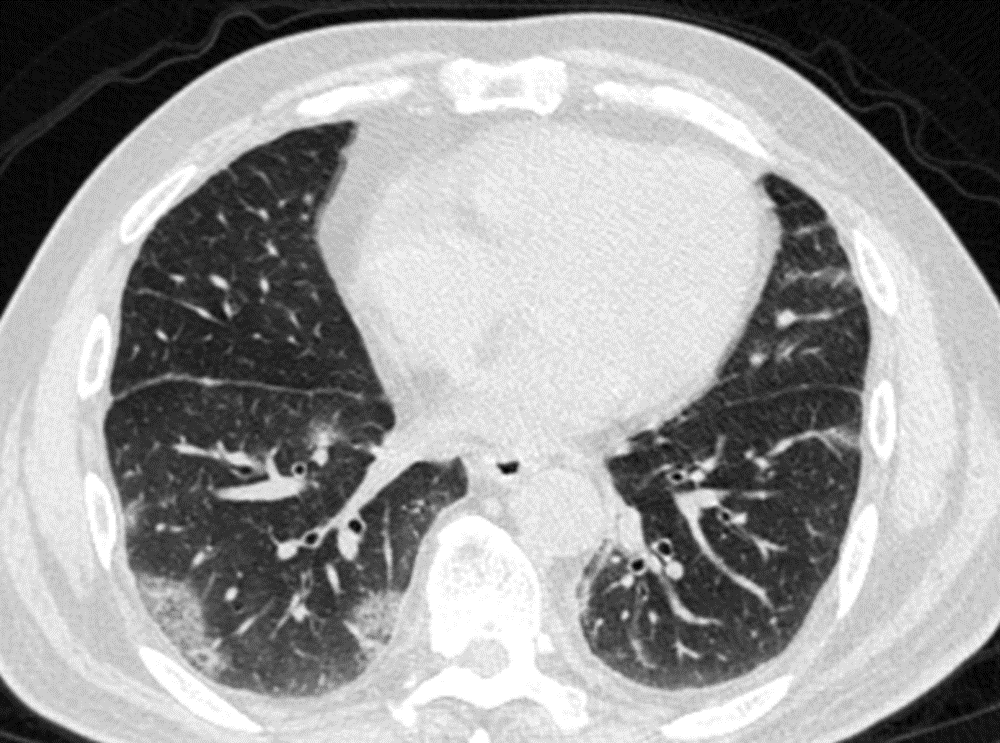

其实,这波omicron感染,确实肺炎比例比想象中要高,但很多都不会是大白肺,多数表现为双肺散发磨玻璃影,当然,也有单独的磨玻璃结节,特别容易表现为混合密度磨玻璃结节。其实很多新发的磨玻璃结节都是新冠肺炎,不用过于紧张,如果感染面积不大,一般临床上,也不需要特异性治疗,休息观察就行了。

可以考虑3个月以后复查一次薄层平扫CT。

CT提示,右肺下叶多发磨玻璃影。